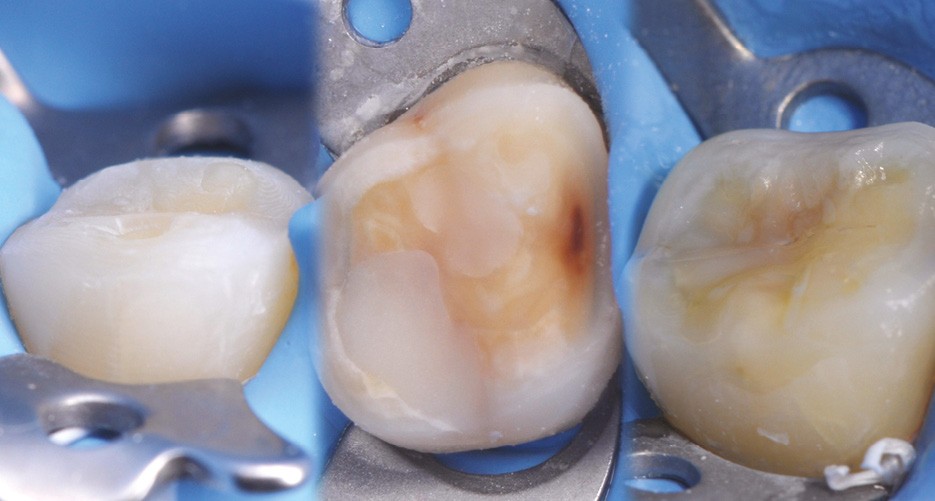

Les overlays (céramique et composite) sont devenus en quelques années un véritable référentiel en termes de restaurations partielles postérieures. Ils sont même les successeurs contemporains de la couronne périphérique dans bon nombre de situations, que ce soit sur dent pulpée présentant un délabrement coronaire important ou sur dent dépulpée pour laquelle le recours au recouvrement de la totalité de la face occlusale est souvent jugé plus indiqué (fig. 1 à 4).

à ces restaurations correspond aujourd’hui toute une série de nouveaux design postérieurs permettant une ultra-préservation tissulaire et pouvant s’inscrire, en fonction des situations cliniques, dans l’émail (situation idéale), dans la dentine, dans le composite de base intermédiaire, ou un « mix » de ces différents supports (fig. 10 à 13).

Les épaisseurs de préparation varient donc selon la nature du support. De 0,6 à 1 mm d’épaisseur sur l’émail jusqu’à 1,5 mm sur la dentine ou le composite afin d’être en adéquation avec les modules d’élasticité des matériaux de restauration utilisés (céramique ou composite).